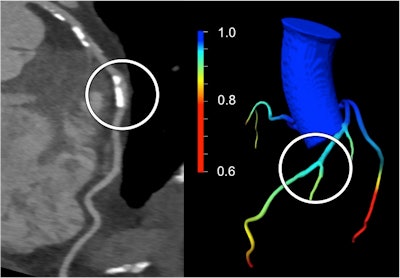

A calcified stenosis in the middle left anterior descending (LAD) artery seen on CCTA (left) was suspected to be significant. However, CT-based FFR demonstrated the absence of lesion-specific ischemia by the color-coded coronary artery tree model (right), which was confirmed by subsequent coronary catheter angiography with invasive FFR derivation. Image courtesy of Dr. Matthias Renker and Dr. U. Joseph Schoepf.The researchers assessed the cFFR software's performance on 67 coronary lesions in 53 patients with suspected or known coronary artery disease who had undergone CCTA on a dual-source CT scanner (Somatom Flash, Siemens) between 2008 and 2014.